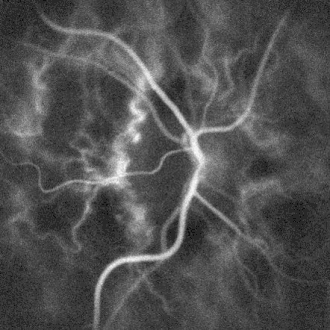

![]() Microangiography of the optic disc region of the human retina, by laser Doppler imaging. The image was rendered computationally by optical wave propagation and measurement of optical fluctuations. | |

The eye offers a unique opportunity for the non-invasive exploration of cardiovascular diseases. LDI by digital holography can measure blood flow in the retina and choroid.[7] In particular, the choroid is a highly vascularized tissue supplying the retinal pigment epithelium and photoreceptors. Yet investigating the anatomy and flow of the choroid remains challenging. LDI provides high-contrast visualization of local blood flow in choroidal vessels in humans, with a spatial resolution comparable to state-of-the-art indocyanine green angiography.[8] Differences in blood pressure drive the flow of blood throughout the circulation. The rate of mean blood flow depends on both blood pressure and the hemodynamic resistance to flow presented by the blood vessels. LDI can enable mapping of the local arterial resistivity index, and the possibility to perform unambiguous identification of retinal arteries and veins on the basis of their systole-diastole variations, and reveal ocular hemodynamics in human eyes.[9]